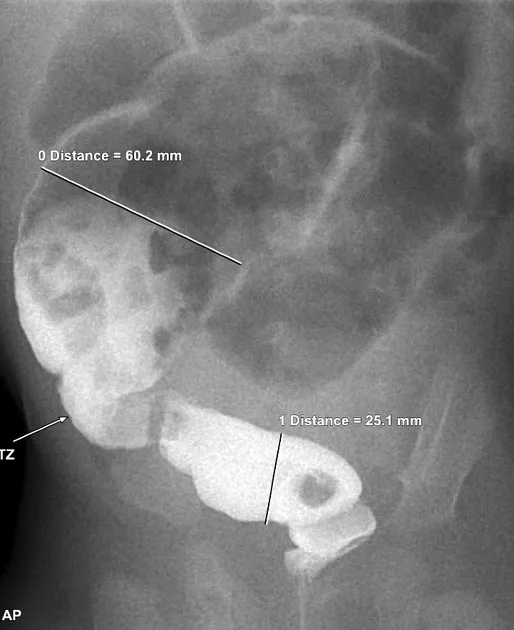

- Contrast Enema: Key initial test. Visualizes a narrow distal segment (aganglionic) and a dilated proximal colon (normally innervated), defining the "transition zone."

- Contrast enema is the best initial imaging test, revealing a transition zone.